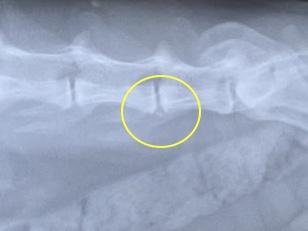

颯士郎の背骨。

言われないとよくわらないけど、変形性脊椎症ですって。

とりあえず一時的に動けなくなった原因が変形性脊椎症かは不明ですが、

今後も気を付けて見ていきましょうということで。

変形性脊椎症(関節症)のためのお注射が今年発売されたとかで、

先生から今後の選択肢として教えていただきました。

ソレンシア?だったかな。

今すぐに必要というわけではないけど、気にはなります。